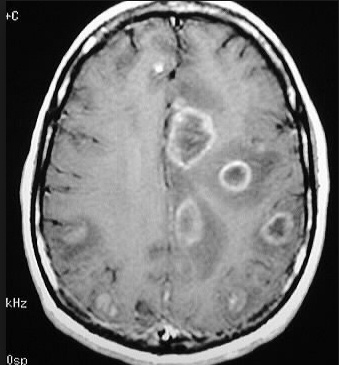

Glio: The CT/MRI findings of a butterfly appearance with central necrosis is classic for GBM, and the heterogenous, serpiginous contrast enhancement is typical of high-grade.

Patients with brain abscess usually have fever, acute onset of symptoms and evidence of a systemic infectious process. On neuroimaging, there is uniform contrast enhancement.

This patient has a primary CNS lymphoma. The presence of EBV DNA in the CSF is specific for this condition. MRI reveals a weakly ring-enhancing mass that is usually solitary and periventricular.

Toxoplasmosis is a good differential diagnosis; however, it is unlikely in this patient since he is receiving trimethoprim-sulfamethoxazole. MRI reveals multiple, ring-enhancing, spherical lesions in the basal ganglia. A positive Toxoplasma serology is quite common in normal subjects in the United States, and is therefore not specific for toxoplasmosis.